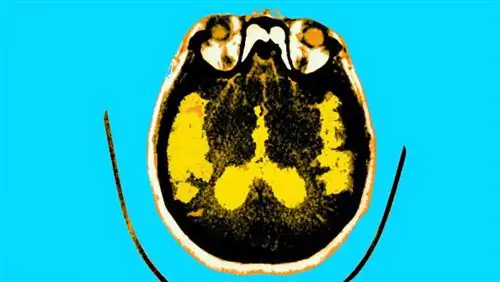

Исследователи из Университетского колледжа Лондона считают, что они обнаружили связь между гормоном роста человека и развитием нейродегенеративного заболевания. Изучая мозговую ткань восьми реципиентов, умерших от болезни Крейтцфельдта-Якоба (БКЯ) после инъекции гормона, ученые обнаружили, что у реципиентов также были признаки раннего начала болезни Альцгеймера. Короче говоря, если болезнь может передаваться через гормоны, то болезнь не может быть полностью генетическим заболеванием.

Конечно, другие ученые сомневаются - в основном потому, что крайне сложно определить пути передачи болезни. Тем не менее, есть доказательства того, что мыши могут заразиться болезнью Альцгеймера, если им вводят белки от пациентов с болезнью Альцгеймера.